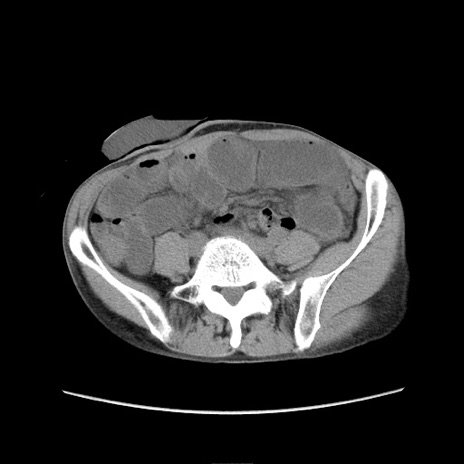

冠状断像

症例11(横断像)

【症例】 60歳代男性

【主訴】 下腹部痛

【現病歴】 本日夜中より下腹部痛の症状認め、受診。

【既往歴】 膀胱癌(膀胱全摘+尿管皮膚瘻術) 、胃癌術後

【身体所見】 BT 35.3℃、PR 58/min、BP 136/98mHg、腹部平坦、軟、腸蠕動音±、ストマ留置あり、左上腹部~正中部に圧痛あり、反跳痛なし。

【データ】WBC 5100、CRP0.01